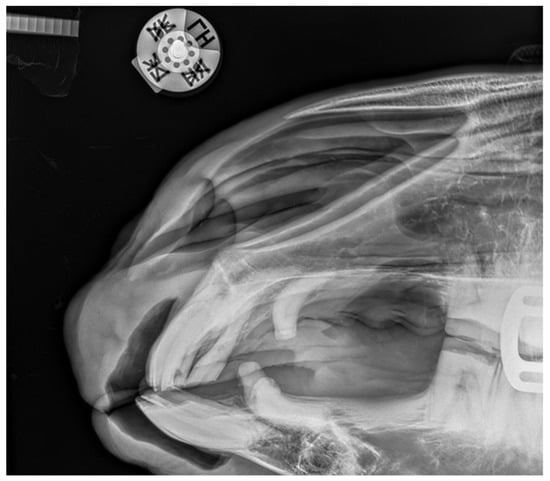

2.1.1. Case 1

2.1.2. Case 2